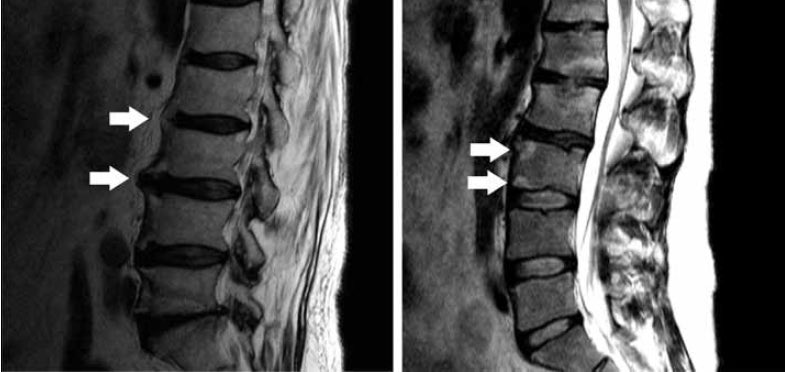

اشعة الرنين mri imaging يتم اتخاذها لتأكيد التشخيص السريري المبني على ماسبق من فحوصات لتأكيد الشكوك، واستبعاد بعض التشخيصات المحتملة الأخرى.